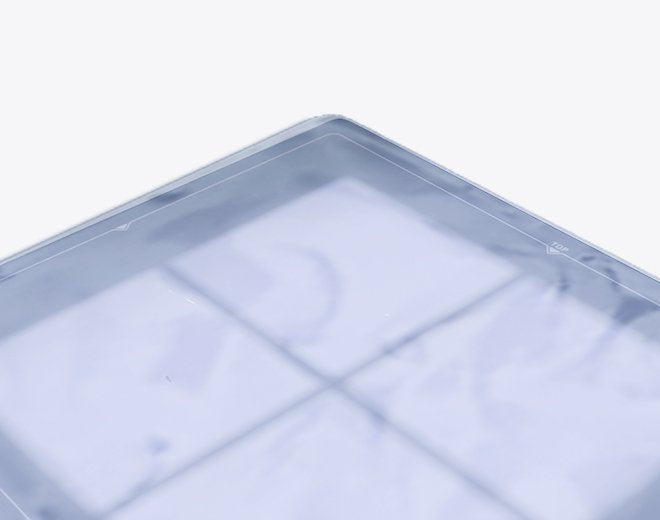

Gigantic Bag’s X-Ray Cassette Covers are designed to protect x-ray cassettes from damage and contamination, ensuring safety and cleanliness in medical environments. These single-use, disposable covers are made from durable, fluid-impervious polyethylene plastic, providing an effective barrier to stop the spread of infection and protect equipment from fluids. Ideal for use in emergency rooms, operating rooms, or with portable x-ray units, these covers deliver trusted performance when it matters most.

- Single-Use and Disposable: Designed for one-time use to maintain hygiene and prevent cross-contamination.

- Durable Construction: Made from top-grade 4-mil polyethylene plastic, ensuring strength and reliability.

- Fluid Impervious: Provides an effective barrier against fluids, safeguarding equipment and preventing damage.

- Variety of Sizes: Available in multiple sizes to accommodate different cassette dimensions, including 24” x 24”.